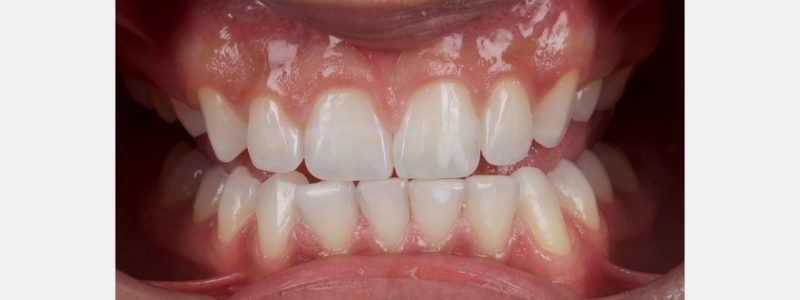

A diagnosis of altered passive eruption (APE) alongside tooth surface loss (TSL) secondary to parafunction was made for a referred female patient in her early 20s who complained of having“short, fat, baby teeth.” Due to her age, she was treated with a simple gingivectomy (after bone sounding), nightguard vital bleaching (NGVB), and additive edge bonding.

The worn incisal edges were restored with edge bonding, a new technique for restoring worn dentition. This should be regarded as a multiple Class IV restoration.